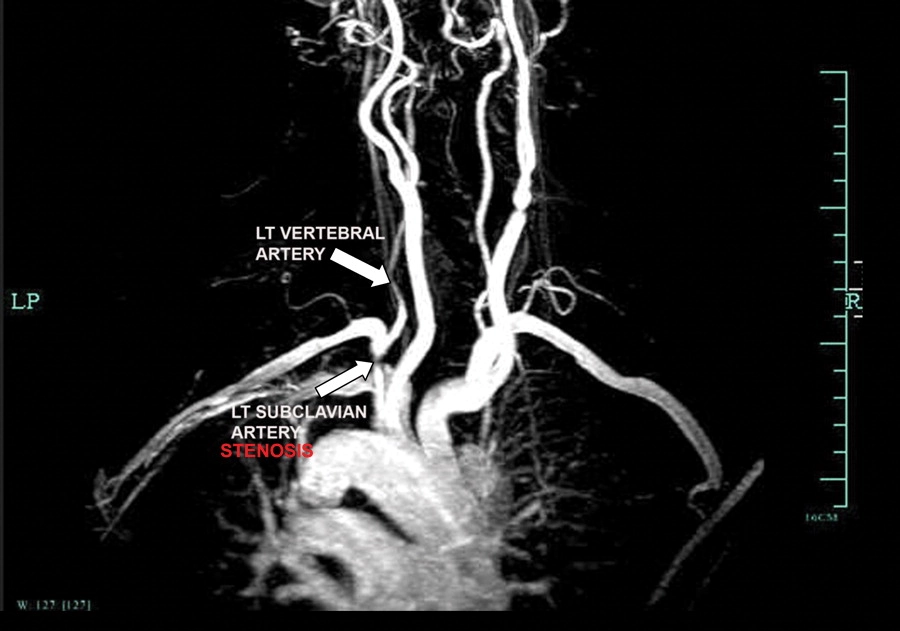

Images visual examples of subclavian steal syndrome

Visual of subclavian steal syndrome often highlight reduced cerebral blood flow and compensatory circulation changes.